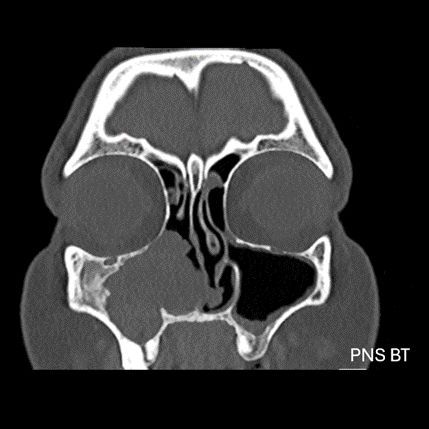

- B) BT incelemesinde maksiller sinüsün duvarları özellikle lateralde daha belirgin olmak üzere reaksiyonel kalınlaştığı izleniyor (oklar). DWI ve ADC haritasında lezyonda belirgin bir kısıtlılık görülmemektedir (oklar).